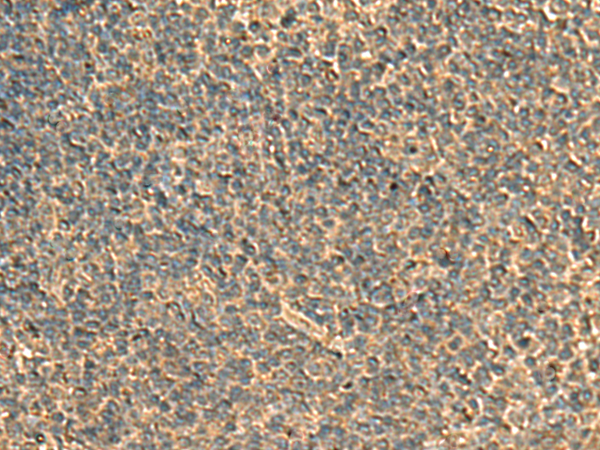

分类: 科研抗体货号: P02832别名:应用: WB,IHC反应种属: Human

分类: 科研抗体货号: P02793别名: HPIP应用: WB,IHC反应种属: Human